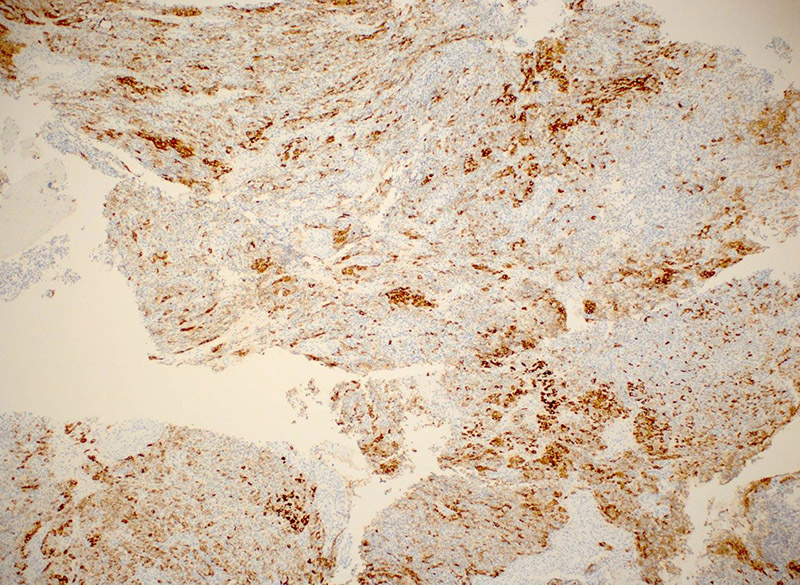

Immunohistochemical (IHC) stains were performed. Both cell populations were positive for inhibin (Figure 5), though more strongly so in the eosinophilic cells, which were also positive for Melan-A (Figure 6). The tumor cells were also positive for pancytokeratin and vimentin, and were negative for EMA.